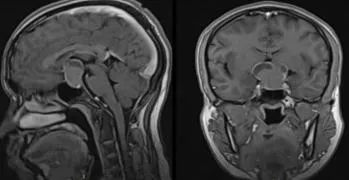

患者男性,24岁,因“轻微头痛伴恶心20余天,加重伴视物模糊7天”入院。查体:青年男性,意识清楚,精神萎靡,双侧瞳孔等大等圆,对光反射灵敏,视力基本正常,第二性征发育差,四肢肌力及肌张力正常,双侧巴宾斯基征阴性。

20.为明确诊断,应立即进行的检查包括

A.颅脑CT检查

B.颅脑MRI检查

C.激素系列检查

D.脑X线平片检查

E.消化道钡餐检查

F.眼底及视力、视野检查

G.脑电图检查

21.提示:患者行颅脑CT检查示轻度脑积水,松果体区高密度影,颅脑MRI检查示松果体区异常信号,3cm大小,T1等信号,T2高信号,均质,增强扫描呈均质显著强化,肿瘤沿三脑室两侧缘生长,钙化的松果体偏离中线。实验室检查示患者AFP及HCG显著增高。初步诊断为生殖细胞瘤。患儿入院3天后,突发昏迷,呼吸微弱,双侧瞳孔略散大,对光反射消失。此时应采取的治疗措施为